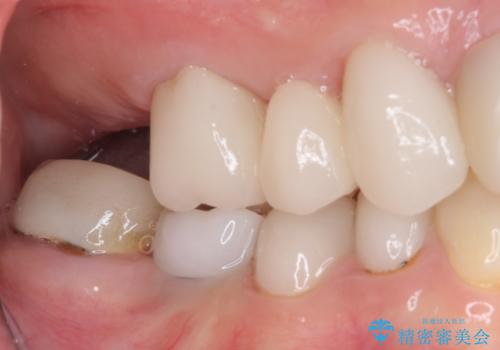

- 虫歯や歯の欠損を放置していることを気にして来院された患者様です。

下顎には抜歯が必要な歯があったため、抜歯後に治癒を待ち、上顎とともにオールセラミックブリッジにて補綴治療を行うこととしました。

治療開始の日に欠損部も含めて仮歯が装着され、今までの不具合や不快感があっという間に改善されました。

抜歯部位の治癒を待つために時間がかかりましたが、来院回数は数回で済み、患者様には大変満足していただきました。